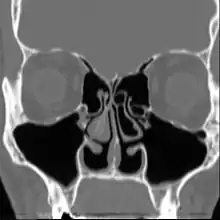

Le syndrome du nez vide (SNV), de l’anglais : Empty Nose Syndrome (ENS), est un état qui apparaît lorsqu'une quantité excessive de tissu nasal producteur de mucus (les cornets ou turbinates en anglais) a été chirurgicalement enlevée du nez ou endommagée, laissant un vide ou des dommages trop importants dans les cavités nasales. Une chirurgie conservatrice peut également mener au syndrome du nez vide car il n'y a pas de standard, ni études, sur la quantité du cornet qui peut être réséquée avant de développer le Syndrome du Nez Vide.

La turbinectomie est la chirurgie de résection totale ou partielle des cornets traitant la portion muqueuse et osseuse.

La turbinoplastie est la chirurgie de résection partielle des cornets agissant uniquement sur la portion muqueuse.

Lorsqu'une quantité excessive des cornets est ôtée ou endommagée, le nez perd ses capacités à convenablement pressuriser, diriger, tempérer, humidifier, filtrer, sentir et détecter le flux d'air inspiré. La synchronisation respiratoire naturelle entre le nez, la bouche et les poumons est également perturbée.